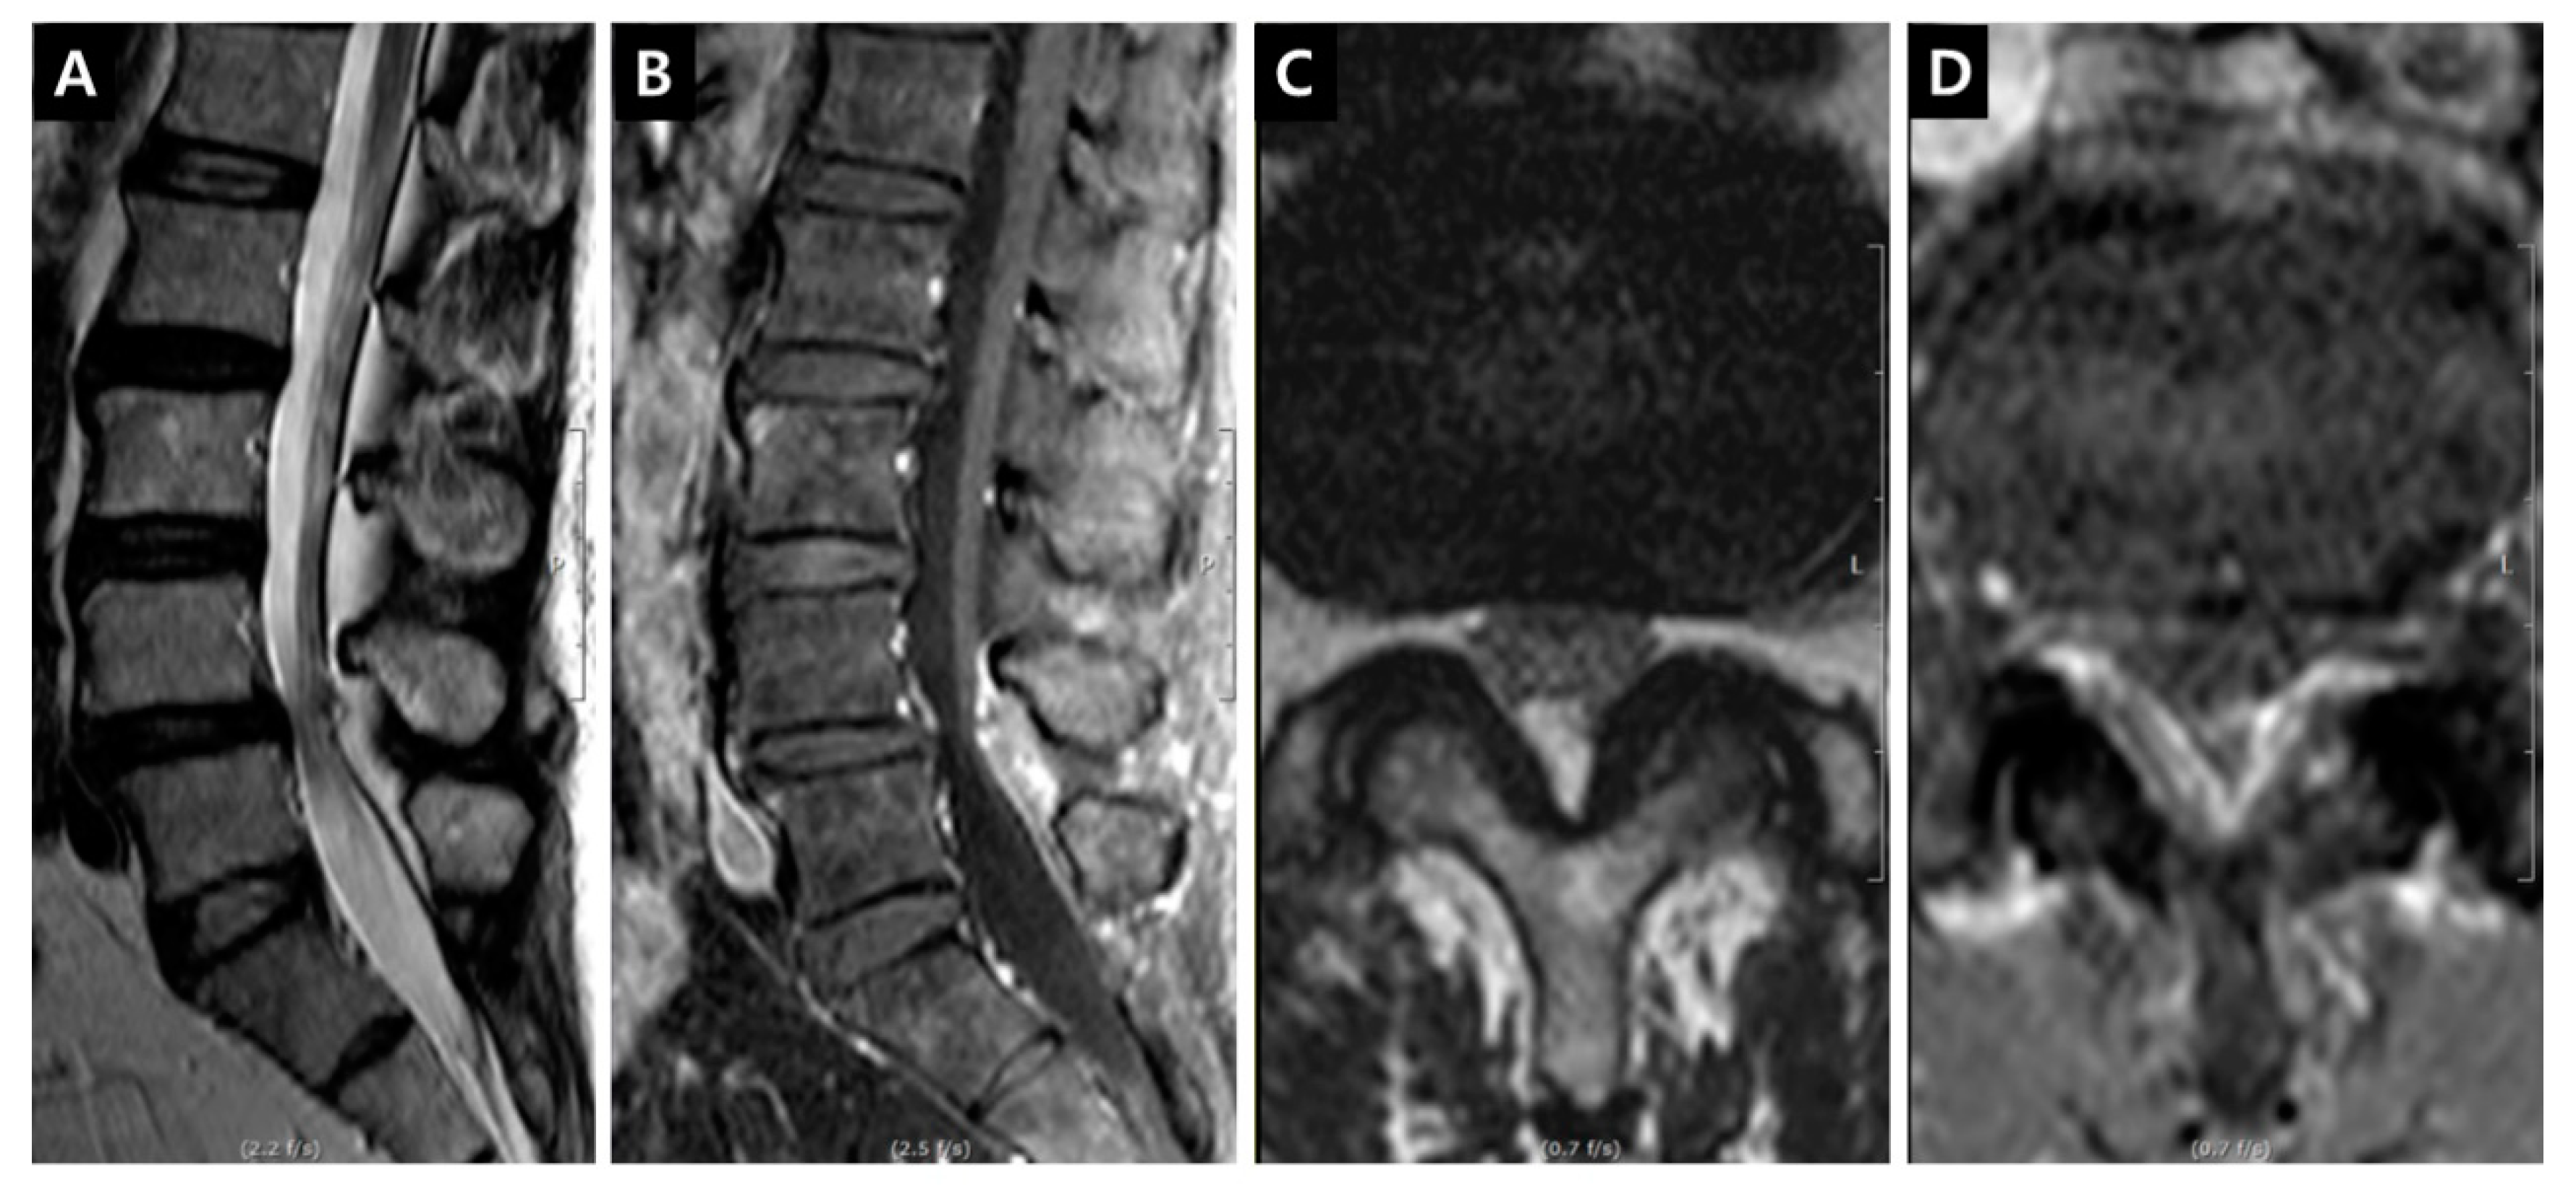

Case 2. Patient (female, 56 years) had complained of bilateral (left > right) buttock and posterior leg pain for 2 months. This case showed the reversibilty of IRCE after decompressive surgeries (Figure 10).

Figure 10. Illustrative Case 2. (A,B) Sagittal MR images revealed the definite central stenosis on L3–4 and L4–5 level; (C,D) Axial images showed IRCEs and the increased enhancement parameters on both levels. For dual lesions, minimally invasive L3 and L4 dome laminoplasties were performed and symptoms improved significantly; (E,F) Five years later, IRCEs on L3–4 and L4–5 level disappeared on follow-up sagittal images; (G,H) The decrease of enhancement parameters corresponded well with all clinical and radiological changes on follow-up axial images.